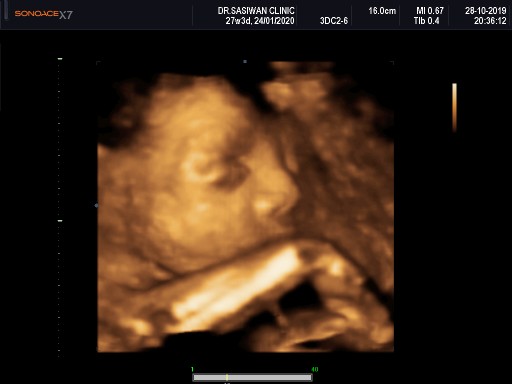

มีบ้านไหนซาวด์แล้วจมูกโด่งแบบนี้มั้ยคะ ออกมาจมูกน้องโด่งแบบนี้รึเปล่า? นี่คุณหมอบอกโด่งมาก?

พุ่งเบาๆค่ะ 😁

รอคลอด ม.ค. ค่ะ